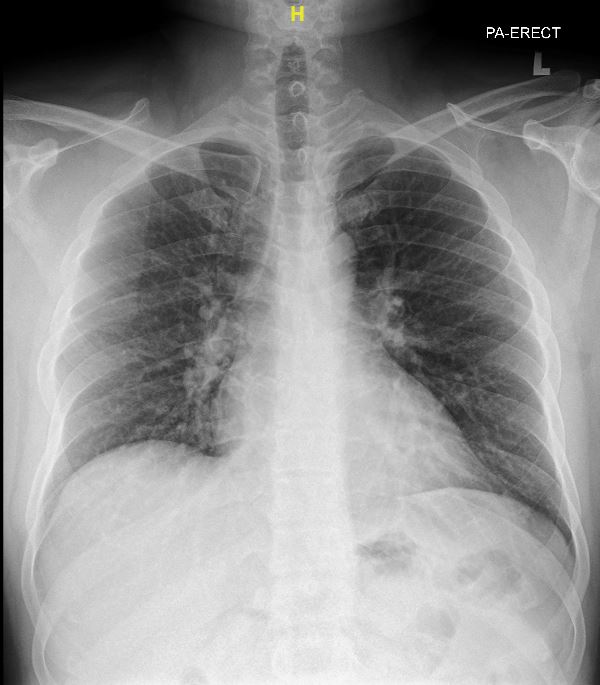

Relevant Test Results Prior to Catheterization

The electrocardiogram shows sinus rhythm, normal axis with left ventricular hypertrophy. The chest X-ray shows a normal cardiac silhouette without prominent pulmonary trunk. His NT-ProBNP was raised with normal troponin reading.The trans-thoracic echocardiogram revealed a ruptured right sinus of valsalva (SOV) with left to right shunting to right ventricle. The aorta is dilated without aortic valve regurgitation. The left ventricle is dilated with 63% of ejection fraction.